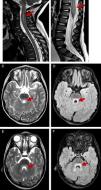

All patients underwent a lumbar puncture, and subsequent examination of the sample revealed pleocytosis in the cerebrospinal fluid in 9 out of 11 patients, with lymphocytic predominance in 7. A MRI scan was performed in 10 patients, revealing rhombencephalitis in 8 (associated with myelitis in 7) and isolated myelitis in 2 (Fig. 1). Since a high proportion of patients presented with somnolence and irritability, an encephalogram (EEG) was performed in 10, revealing slow wave activity in 9. The results of 9 brainstem auditory evoked response tests in patients with manifestations or MRI evidence of brainstem involvement and the 3 electromyograms performed in patients with significant spinal cord involvement were normal.

T2-weighted and FLAIR MR images showing hindbrain involvement with myelitis. T2-weighed images showing hyperintensity on at the level of the cervical spine until segment C6 in patient 2 (A) and significant thickening of the conus medullaris in patient 4 (B). Hyperintensity on T2-weighted and FLAIR MR images at the level of the posterior pons and surrounding the fourth ventricle in patient 2 (C–F).